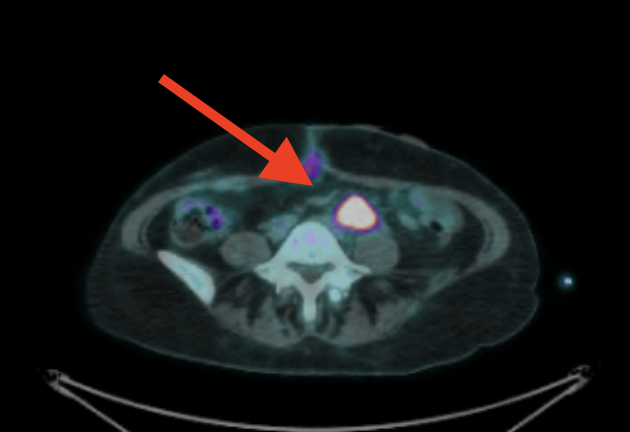

I've had 3 scans. First scan it was 3cm with a SUV max score of 5 point something. (For my type of cancer, 2.5 or above is considered cancerous... it's how much of the radioactive stuff is detected in the spot. Or something like that.) My second scan it was about 1 cm with a SUV max score of I think 2.6. Then this last scan it was still 1 cm but the SUV max score was 1.9. I'd have to log back in to confirm those numbers but that's what I recall.

February: 3 cm:

June: 1 cm with inflammation at the staple line of my Hartmann's pouch:

September: Inflammation resolved, spot still 1 cm (but no FDG uptake):

Previously depicted left retroperitoneal nodal mass in the common iliac station measures 0.9 cm in short axis, unchanged (SUV max 1.9, previously 2.6, image 224). Elsewhere below the diaphragm, tracer activity is unremarkable. Calcified mass closely associated with bowel in the left hemiabdomen is unchanged. Left renal cyst. There are postoperative changes of the colon with left lower quadrant ostomy. There are no FDG avid skeletal lesions.

No findings convincing for FDG avid malignancy. The left common iliac nodal lesion is not FDG avid and is similar in size to the prior study.